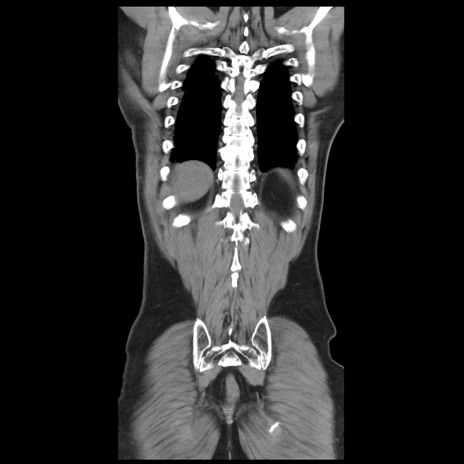

症例20(冠状断像)

【症例】 60歳代男性

【主訴】 腹部膨満、嘔吐

【現病歴】5日前頃より倦怠感を認め食事量減少し4日前の朝嘔吐、食事摂取困難となった。 3日前近医受診し点滴施行され整腸剤などを処方された。 当日他院を受診し、腹部膨満著明、炎症反応の上昇(CRP10.8、WBC11200)あり、紹介受診となる。

【身体所見】 意識JCS1 受け答えがはっきりしないBP 111/57mHg、 P 67bpm、、BT35.2°C、SpO2 97%(RA)、 腹部:膨隆、打診で鼓音あり、全体的に圧痛有り、腸蠕動音(-)、反跳痛ははっきりせず。

【データ】WBC 11400、CRP 14.20